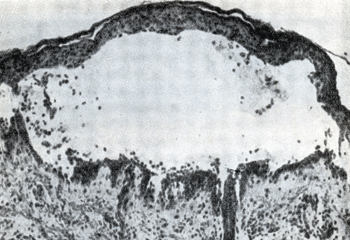

Ականտոլիզիսի հետևանքով լայնացած միջբջջային տարածություններում կուտակվում է հյուսվածքային հեղուկ, որի պատճառով լորձաթաղանթների և մաշկի մակերեսի վրա բշտեր են ձևավորվում (նկ.4):

Նկար 4. Բուշտ սովորական բշտախտի ժամանակ

Ախտահյուսվածաբանական հետազոտություն: Ախտահարված լորձաթաղանթից կամ մաշկից վերցրած բիոպտատում հայտնաբերվում են ներէպիթելային դասավորությամբ ճեղքեր և բշտիկներ` լցված հյուսվածքային հեղուկով, հնարավոր է նաև ականտոլիտիկ բջիջների պարունակությամբ: